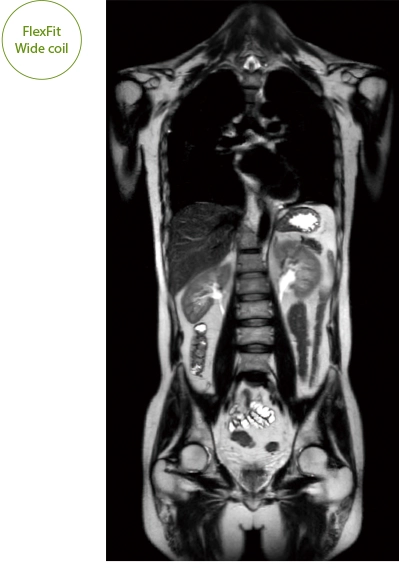

"DLR" is applicable to all body parts and promotes high speed imaging and diagnostic efficiency

IP-RAPID x DLR Plus can also shorten imaging time, allowing more images to be taken in the same examination time.

Additional imaging, such as different image types and cross sections, can be added to the conventional examination to increase the amount of information and make the diagnosis more reliable.

It can also be used with time-consuming scans such as Whole Body DWI and Whole Spine imaging, providing more detailed information in many areas than previously possible.

The ECHELON Synergy ZeroHelium is equipped with a flexible head and neck coil that allows one-action setup via sliding installation, as well as a Flex coil that provides wide and flexible coverage of the imaging area. This enables flexible adaptation to different part of body.